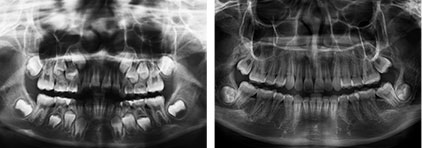

整個矯正的療程要定期追蹤回診,我們定期至少每2~3個月會對口內及外型的做一個完整的照相紀錄,紀錄矯正期間臉型及齒列的各種變化,適時的修正與調整。

矯正治療要對整個臉型做精密的計算和預測,本院也提供矯正前後的口內照片、外型照片、3D斷層攝影、2D全口、側顱、正顱X光的拍攝。待矯正完成後再提供一付矯正維持器,確保矯正後的牙齒可以維持在最好的位置。